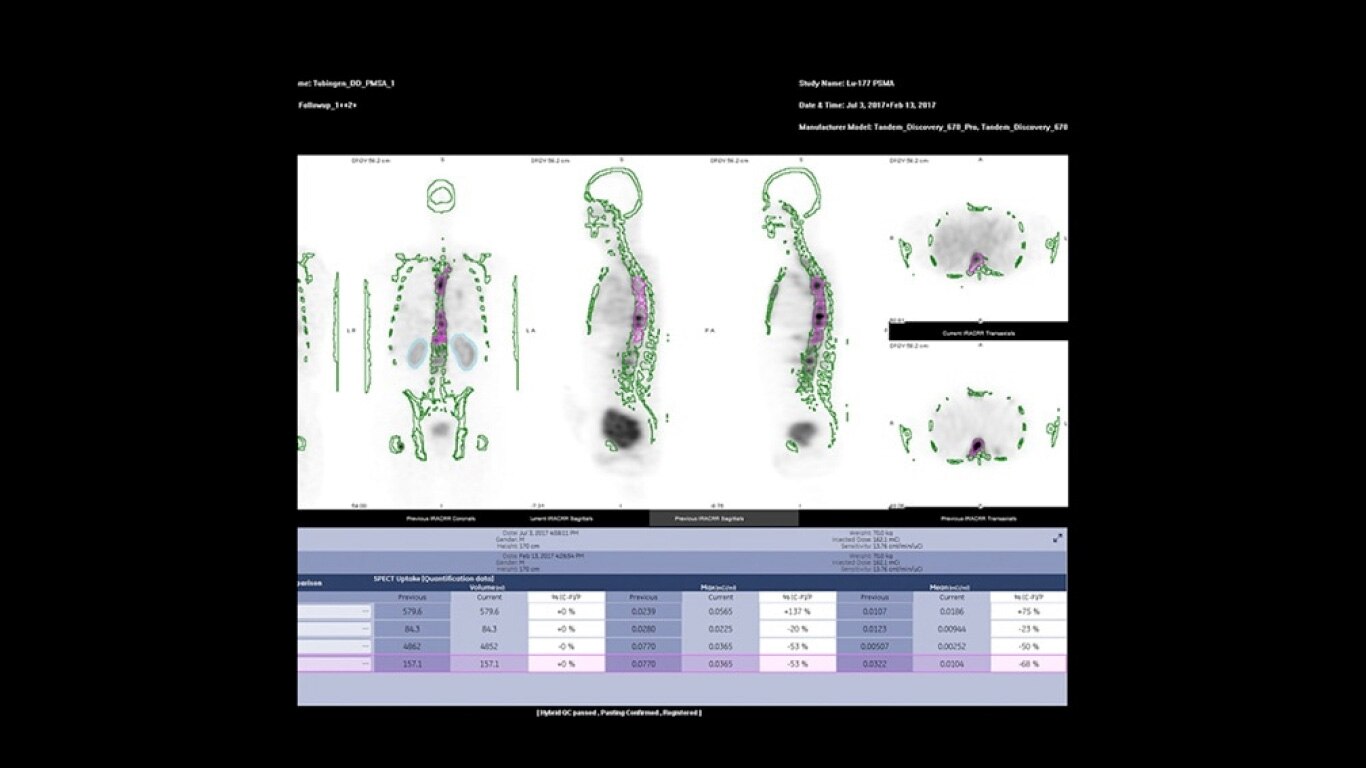

Experience a new productivity hub for hybrid imaging. By automating SPECT/CT reconstruction, SmartConsole simplifies the workflow for complex hybrid and quantitative protocols and allows technologists to review results directly at the scanner console. It also allows physicians to review scans remotely from mobile devices. They can modify processing settings and initiate study processing anytime, anywhere across a LAN or a WAN*.

SmartConsole enables a noticeable improvement in productivity. Now, a physician can provide their input remotely and digitally. For example, physicians can review a whole-body bone scan directly on their tablet or other mobile device and define the scan range limits they need from wherever they are. The time saved with this switch to a digital workflow helps make it possible to complete exams in predictable time slots.